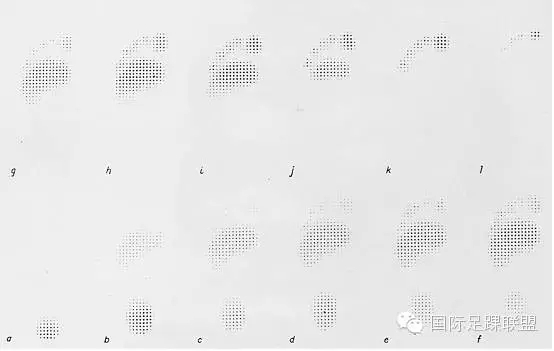

最早的直接测量手段是根据材料的物理特性来获得足与地面的相互作用。将足置于粘土、石膏或土壤中,通过脚印的深浅来判断足底压力的分布。应用材料包括橡胶垫结合纵脊、锥形投影或多层网格(如Harris-Beath垫)等,当站立或在行走于其上时,产生的压力与材料凹陷的程度成正比,进而可以对足底进行测量(图1)

图1 通过压力计测量的足底压力分布。图中点的密集程度与延伸深浅与该区域压力的大小呈正相关(引自 Elftman H: A cinematic study of the distribution of pressure in the human foot. Anat Rec 59:481-491, 1934.)。